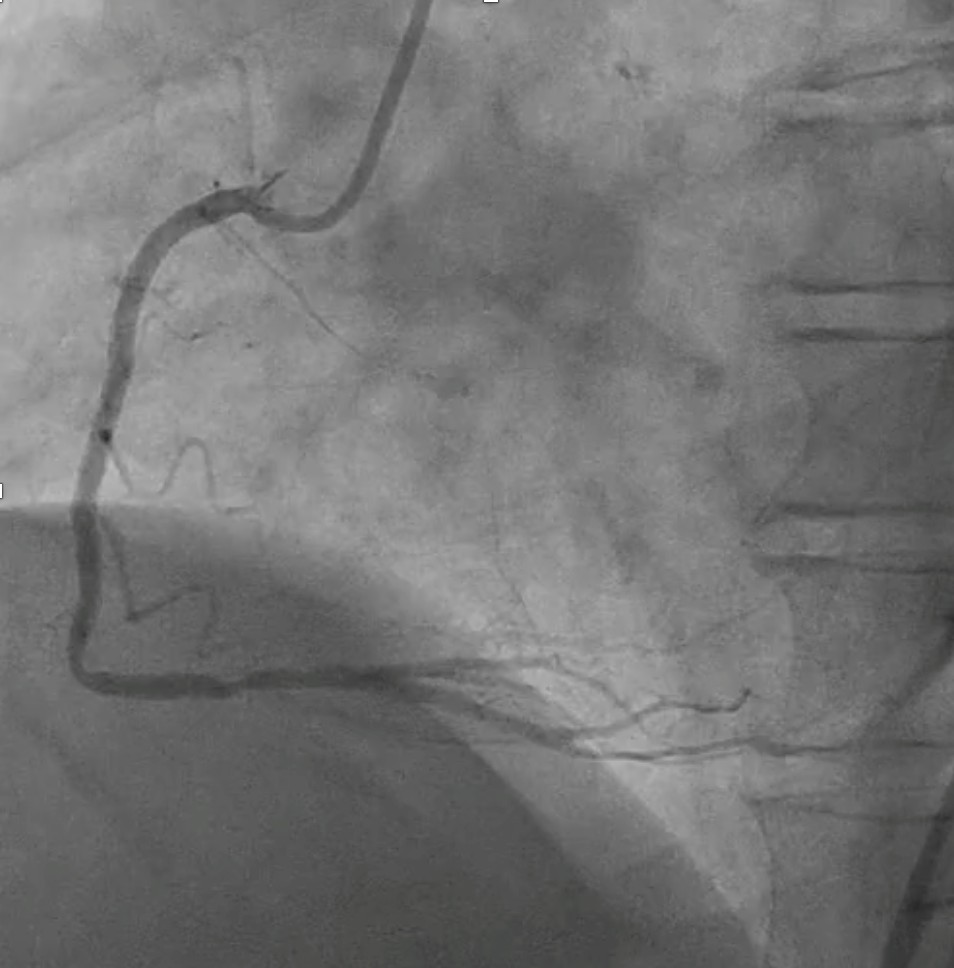

Initial angiography at our facility revealed patent stent at osteal to mid RCA.Left coronary angiography showed patent stent at proximal to distal LCx anddiffuse, severe and heavy calcified stenosis at proximal to distal LAD.

PCIof the LAD was performed via femoral access using a BL 3.5/7F guiding catheter.A Runthrough Hypercoat wire was advanced distally without difficulty. The OCTcatheter failed to cross the lesion, and a 2.5 ¡¿ 15 mm scoring balloon couldnot pass the mid LAD. A microcatheter was inserted, and the wire was exchangedfor a Rotawire. Rotational atherectomy was performed using a 1.25 mm burr withshort, gentle pecking runs at 180,000 rpm, followed by upsizing to a 1.5 mmburr for three runs at 200,000 (2 times) and 160,000 rpm. The burr advancedsmoothly with improved tactile feedback, suggesting successful plaquemodification. The wire was exchanged back to a Runthrough, and OCT (DragonflyOPTIS) imaging showed an MLA of 1.43 mm©÷ at mid LAD with severe 360¡Æ calcification(0.9 mm thick, 41 mm long) and a napkin-ring pattern. A 2.5 ¡¿ 15 mm cuttingballoon was used with multiple 14–18 atm inflations, producing a visible¡°crack¡± in the calcified cap. Angiography and repeat OCT confirmed the calciumfracture. A 3.0 ¡¿ 46 mm DES was deployed from the ostial to distal LAD at 14atm and post-dilated with a 3.5 mm NC balloon proximally. Final angiographyshowed TIMI 3 flow. OCT demonstrated excellent stent expansion (MSA 7.78 mm©÷proximal, 3.28 mm©÷ distal) without dissection and with 107% stent expansion.